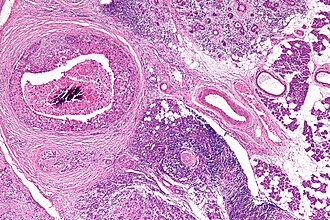

Salivary duct carcinoma. H&E stain.

LM varied arch. (sheets, nests, cords, cribriform, micropapillary), neoplastic cells line-up around cystic spaces "Roman bridges", nuclear atypia, apocrine snouts, decapitation secretions

Features - resembles ductal breast carcinoma:[1]

• Architecture: sheets, nests, cords, cribriform, micropapillary.

• Neoplastic cells line-up around cystic spaces "Roman bridges".

• Nuclear atypia (variation in size, shape, staining).

• Apocrine snouts - pseudopod-like/lollipop-like undulations of the cell membrane.

• Decapitation secretions - apocrine snouts (membrane bound blobs of cytoplasm) that have separated from its mother cell.

• Similar to ductal breast carcinoma - key to remember.

Salivary duct carcinoma. 59 y man with a 3 cm right superficial parotid mass. A. Low power shows a predominance of patterns similar to in situ, micropapillary (white arrow), Roman bridge (green arrow), cribriform (blue arrow) patterns. B. Careful search reveals occasional invasive bars (arrow). C. The bar comprises the usual invasive pattern of adenocarcinoma, with cancerous cell clusters, isolated glands, incomplete glands, and adjoined/fused glands. Note the lighter color of stromal desmoplasia (arrows). D. The in situ component has more uniform nuclei than the invasive component. Note the comedo necrosis. E. Cancer cells expressed CK7. F. Cancer cell nuclei were positive for androgen receptor. Not shown: tumor was negative for SOX10 and P63.